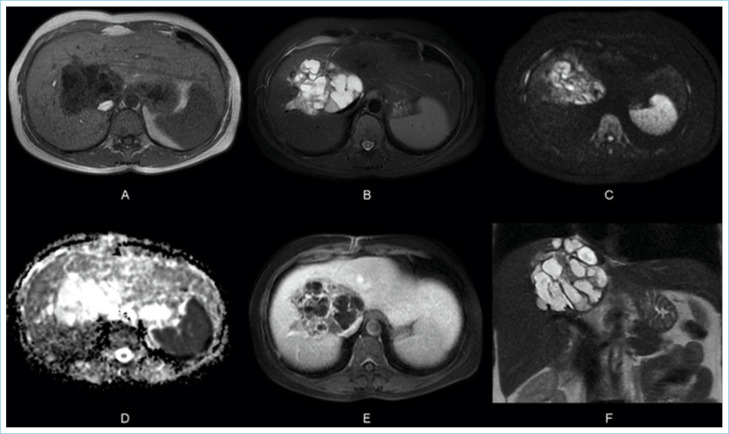

Biliary cystadenomas are uncommon lesions with clinical and radiological characteristics that overlap with other cystic liver lesions. Here, we intended to discuss a biliary cystadenoma found in a 37-year-old female patient who had been treated for a liver abscess and had been sent to our clinic with a long-term hydatid cyst diagnosis.

Abstract Image